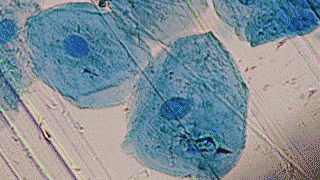

在哺乳动物中,性别是由染色体决定,XX为雌性,XY为雄性。

但是实际上染色体只是决定性别的一个方面,真正的性别分化需要精确的基因表达程序。

哺乳动物决定性别有一个关键的基因,叫SRY,它就像启动雄性发育程序的开关,位于Y染色体上,如果这个开关顺利打开,胚胎就会发育出睾丸。

如果是雌性XX染色体,因为没有Y染色体,也就没有这个开关,自然就直接发育成卵巢。

这个SRY基因开关需要靠一个叫KDM3A的酶来打开。关键来了,这个酶需要一个特定工具才能有效工作,这个工具就是亚铁离子(Fe2+)。没有足够的亚铁离子,KDM3A就没有办法工作,SRY开关就打不开。